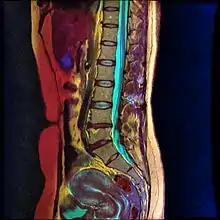

Lumbar sympathetic neurolysis is performed between the L1-L4 vertebrae with separate injections at each vertebra junction. The chemicals used for neurolysis of the nerves cause destructive fibrosis and cause a disruption of the sympathetic ganglia. The vasomotor tone is decreased in the area affected by the neurolysis, which in addition to arteriovenous shunting, create a light pink appearance within the affected area. Lumbar sympathetic neurolysis alters the ischemic rest pain transmission by changing norepinephrine and catecholamine levels or by disturbing afferent fibers. This procedure is mainly used only when other feasible approaches to pain management are unable to be used.[6]

Lumbar sympathetic neurolysis is performed by using absolute alcohol, but other chemicals such as phenol, or other techniques such as radiofrequency or laser ablation have been studied. To aid in the procedure, fluoroscopy or CT guidance is used. Fluoroscopic guidance is the most frequent, giving better real-time monitoring of the needle. The general technique of administering lumbar sympathetic neurolysis involves using three separate needles rather than one because it allows for better longitudinal spread of the chemicals.[6]